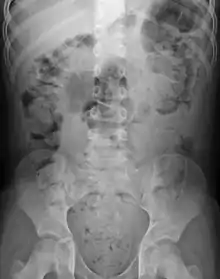

| Constipation in a young child seen on X-ray. Circles represent areas of fecal matter (stool is white surrounded by black bowel gas). | |

Abdominal X-rays are generally only performed if bowel obstruction is suspected, may reveal extensive impacted fecal matter in the colon, and may confirm or rule out other causes of similar symptoms.[25][17]